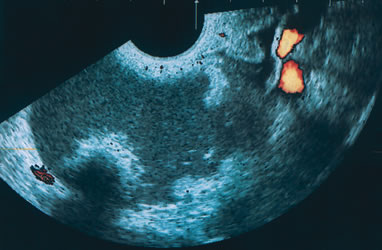

Fig. 1. Three-dimensional orthogonal images of a simple 4-cm cyst in a premenopausal woman. The image in the bottom right is a rendering of a portion of the inner cyst wall. No excrescences were noted. The cyst resolved spontaneously.